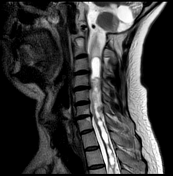

2 — RM de coluna total com contraste

- T1 e T2 sagital cobrindo toda a coluna.

- Cortes axiais nos níveis suspeitos.

- Pós-contraste para detecção de hemangioblastomas medulares.